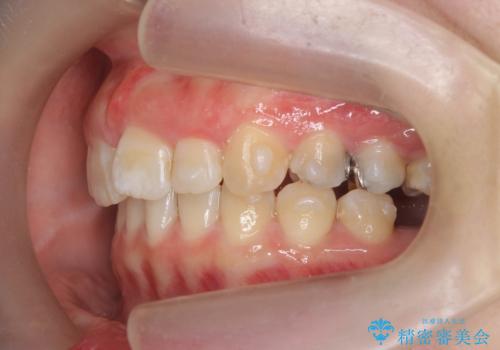

- 大きくねじれた前歯をまっすぐに並べたい。と矯正治療を希望され来院されました。

前歯をきっちり並べるには奥歯の噛み合わせの調整を行い上下の前後的関係を治し、ねじれを取るスペースを確保していきます。

当初前歯だけ治れば良い、という心算で来院されましたが奥歯の噛み合わせも負担が大きく問題の起きやすいことをお伝えし上顎の奥歯をきっちりと後方移動行い噛み合わせの調整を行いました。・